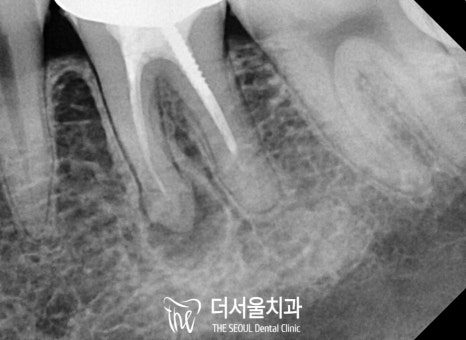

파노라마 사진을 촬영해 봤더니

눈에 띄지 않는 곳에도

치석이나 우식이 존재했습니다.

우선 본원에서는 불편함을 느끼고 있던

아래 어금니부터 순차적으로

개선을 돕기로 했는데요.

“ 26번 교정 전 신경치료,

36번 리엔도 (re-endo)로

썩은 곳을 깨끗이 없애기로 했죠. ”